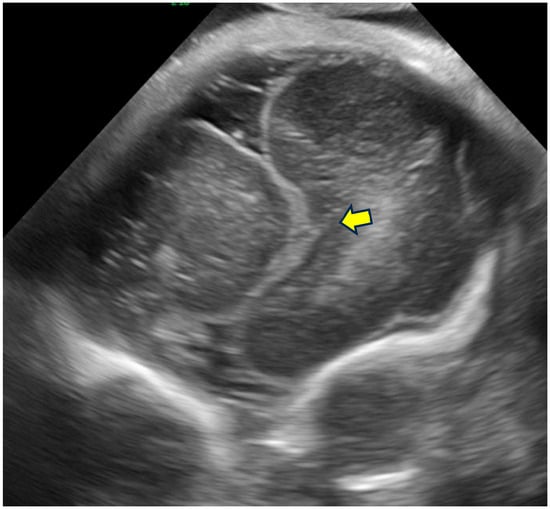

The Role of Prenatal Neurosonography in Identification of Tubulinopathy—Narrative Review